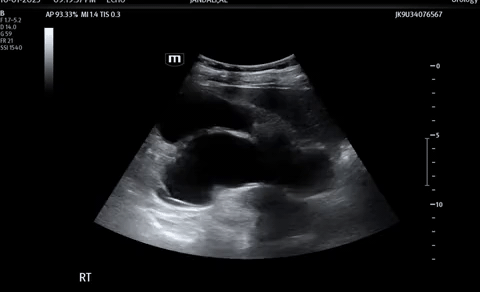

A 70 year old male presenting with worsening right flank pain over the last two days.

Ultrasound of his right kidney revealed…

Bedside POCUS

A renal/bladder POCUS was performed to evaluate for any secondary signs of obstruction.

These images demonstrate severe hydronephrosis with obvious loss of renal architecture.

Renal cysts often mimic hydronephrosis.

- However, simple cysts are usually thin walled, without septations, localized to the periphery and do not connect to calyces.

- Always scan in both planes to help differentiate the two.